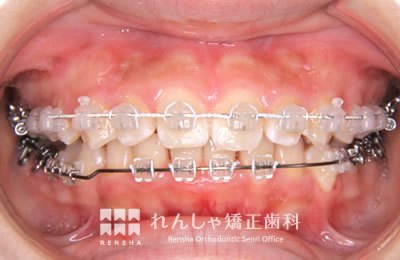

中高生

永久歯列はほぼ完成してしますが、歯列を側方だけでなく後方へも拡大し、埋まっていた右上奥歯を引っ張り出しています。

治療中

→

治療後

| 主訴 | 埋まったままでてこない歯がある |

|---|---|

| 診断名 | Angle Class II 小臼歯の埋伏と叢生を伴う上顎前突 |

| 初診時年齢 | 13歳5か月 |

| 装置名 | マルチブラケット装置 |

| 抜歯非抜歯 | 非抜歯 |

| 治療期間 | 2年3か月 |

| 費用の目安 | 約82万円+消費税(検査料金、都度の処置費用等も合わせた総額) |

| リスク副作用 | 歯の移動に伴う軽微な歯根吸収、歯槽骨吸収、歯肉退縮(本症例では軽度の歯根吸収を認めた)、矯正器具装着中のカリエスリスク増大(本症例ではカリエス発生無し) |